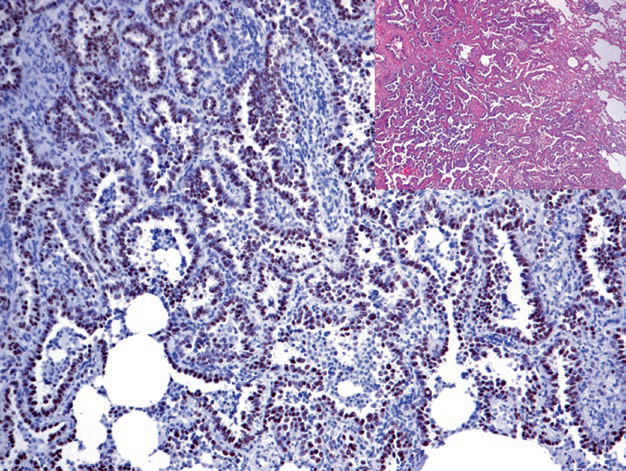

图片

Figure 1. Strong nuclear positive expression of TTF-1 in pulmonary small cell carcinoma.

Figure 2. Strong nuclear positive expression of TTF-1 in pulmonary adenocarcinoma.